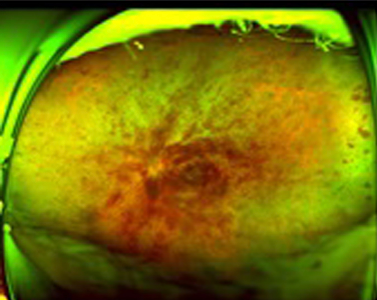

網膜の血管が詰まると、静脈から網膜に血液成分が漏れだし、出血が生じ、網膜の中心である黄斑に水があふれて腫れます。

これを黄斑浮腫と言い、網膜静脈閉塞症の視力低下の原因です。

中心静脈という網膜静脈の根元で詰まります。あふれ出た血液が網膜全体に広がります。急激な視力低下が起こり、黄斑部の浮腫が起こるとゆがみが見られ、視力も下がります。